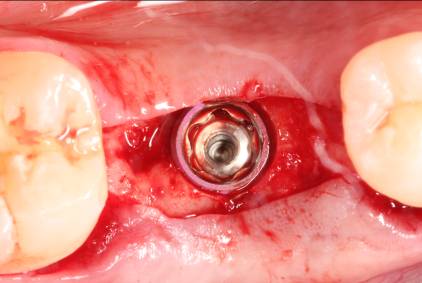

In February 2012 the patient enrolled in the multicenter study, and a 5.5-mm x 11.5-mm implant (Genesis) was placed (Figure 42). Minor contour bone grafting of the site was also performed using autogenous bone directly against the buccal cortex and layered thereafter with a corticocancellous allograft (Puros) along the lateral aspect of the implant. This was done to increase the peri-implant bone and mucosal thickness (existing bone thickness was <1 mm on the buccal aspect) in an effort to improve parameters that would reduce the incidence of recession over the long term.

The 5.5-mm implant platform was used to accommodate the high occlusal load typically associated with the molar area and to optimize the esthetic emergence profile of the final restoration, neither of which would have been feasible with a narrower implant, even in the presence of more robust socket augmentation. A healing abutment was placed (Figure 43).